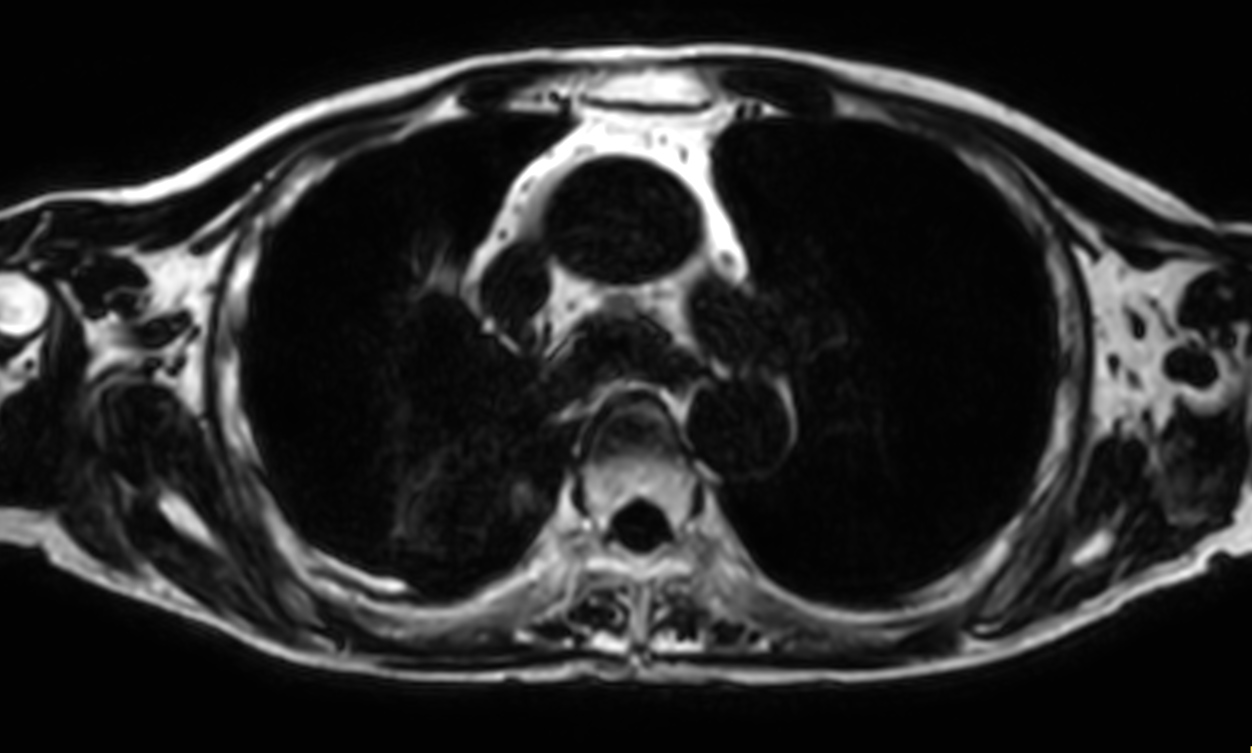

Patient with lung cancer. The ExamCard includes techniques for efficient fat-free imaging over large field-of-views (mDIXON XD), a diffusion procedure with less distortion (DWI TSE XD), a multi-phase contrast-enhanced sequence (4D FreeBreathing) to improve imaging confidence and Compressed SENSE to accelerate the entire exam.

T1w mDIXON XD FFE (Water only) Compressed SENSE